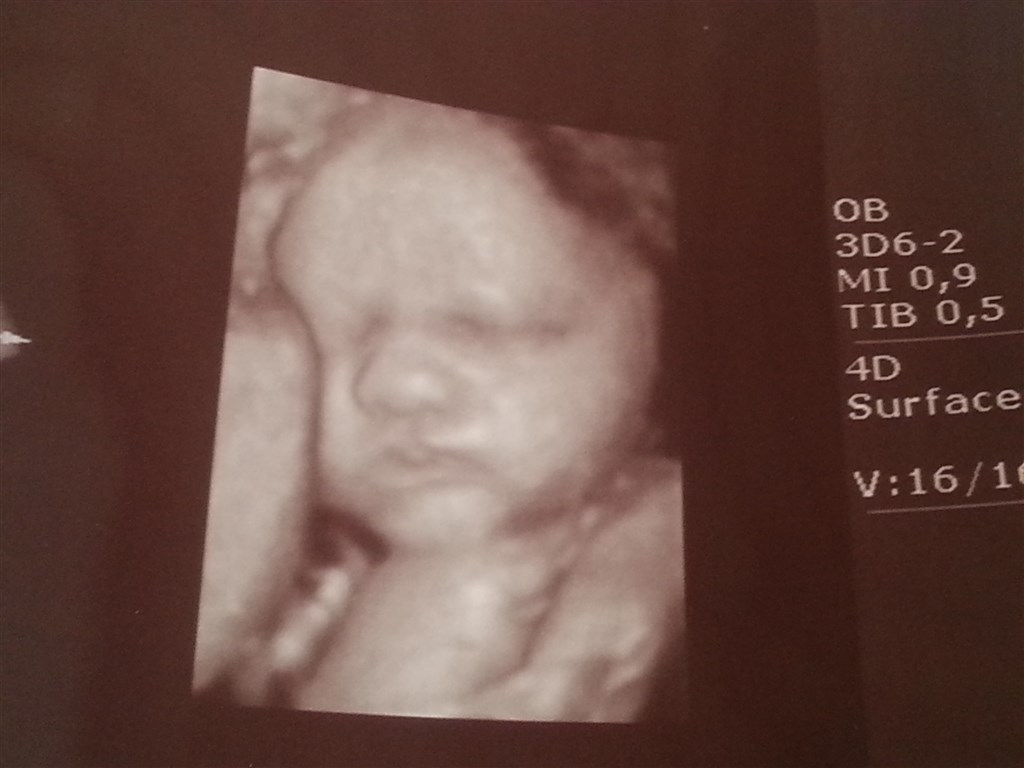

Nogen der har fået 3D alligevel(bare kort) selvom det var kønsscanning ?